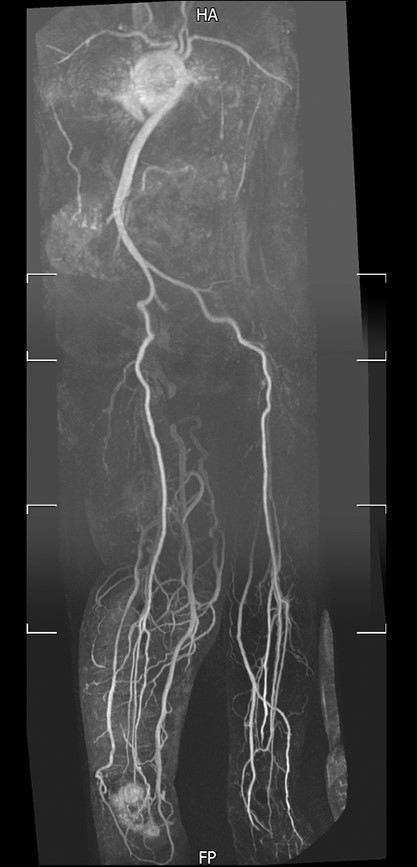

Magnetic resonance imaging and a SPECT-CT (single photon emission computed tomography-CT) were requested which showed osteomyelitis in the bone around the Girdlestone and in the calcaneum. Vascular assessment revealed a normal arterial supply (Fig. 1).

Magnetic resonance angiography of lower limbs. Magnetic resonance angiography showed a normal peripheral arterial supply to both lower limbs.